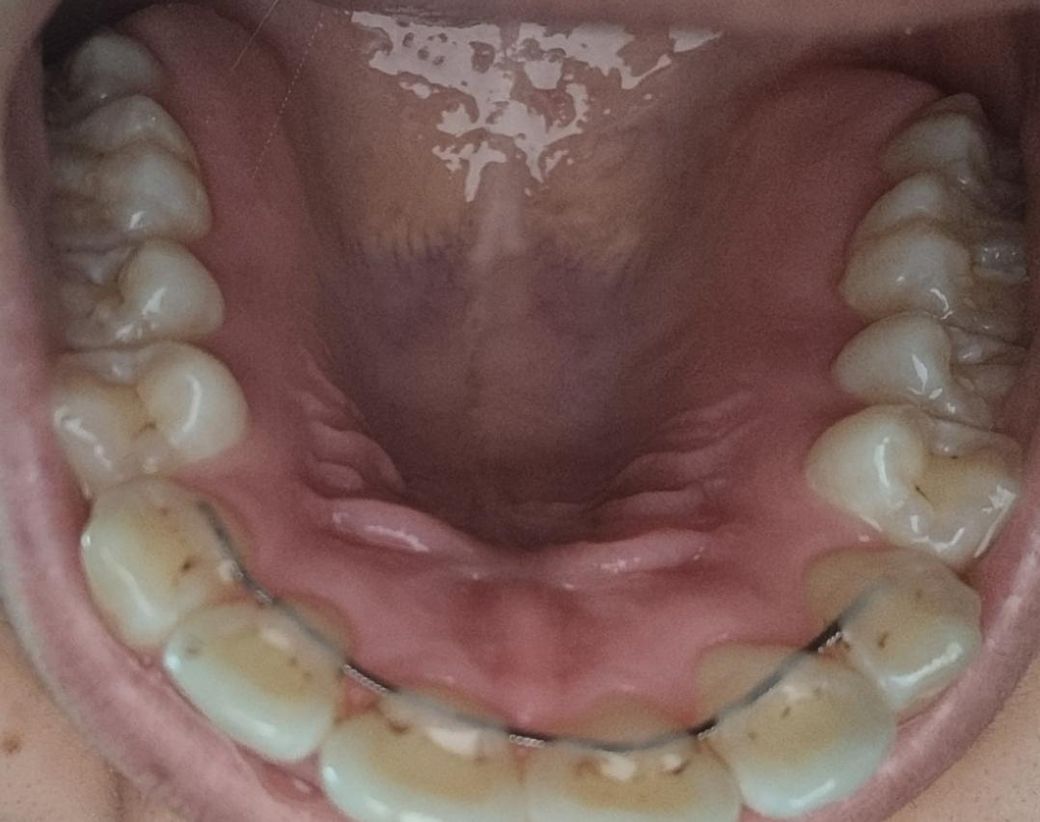

유지장치 주변 이랑 어금니 변색 정리 가능한지

작년 10월에 스케일링 받고 아직 1년이 안돼서 스케일링 하긴 힘들 것 같긴 한데요 치과에서 어금니도 변색이라 하고 유지 장치도 안 떼고 변색만 정리 가능할까요?

• 1번 째 사진

유지 장치도 안 떼고 변색만 정리 가능할까요? -> 어느정도는 가능하지만 완전히 제거하긴 어렵습니다.